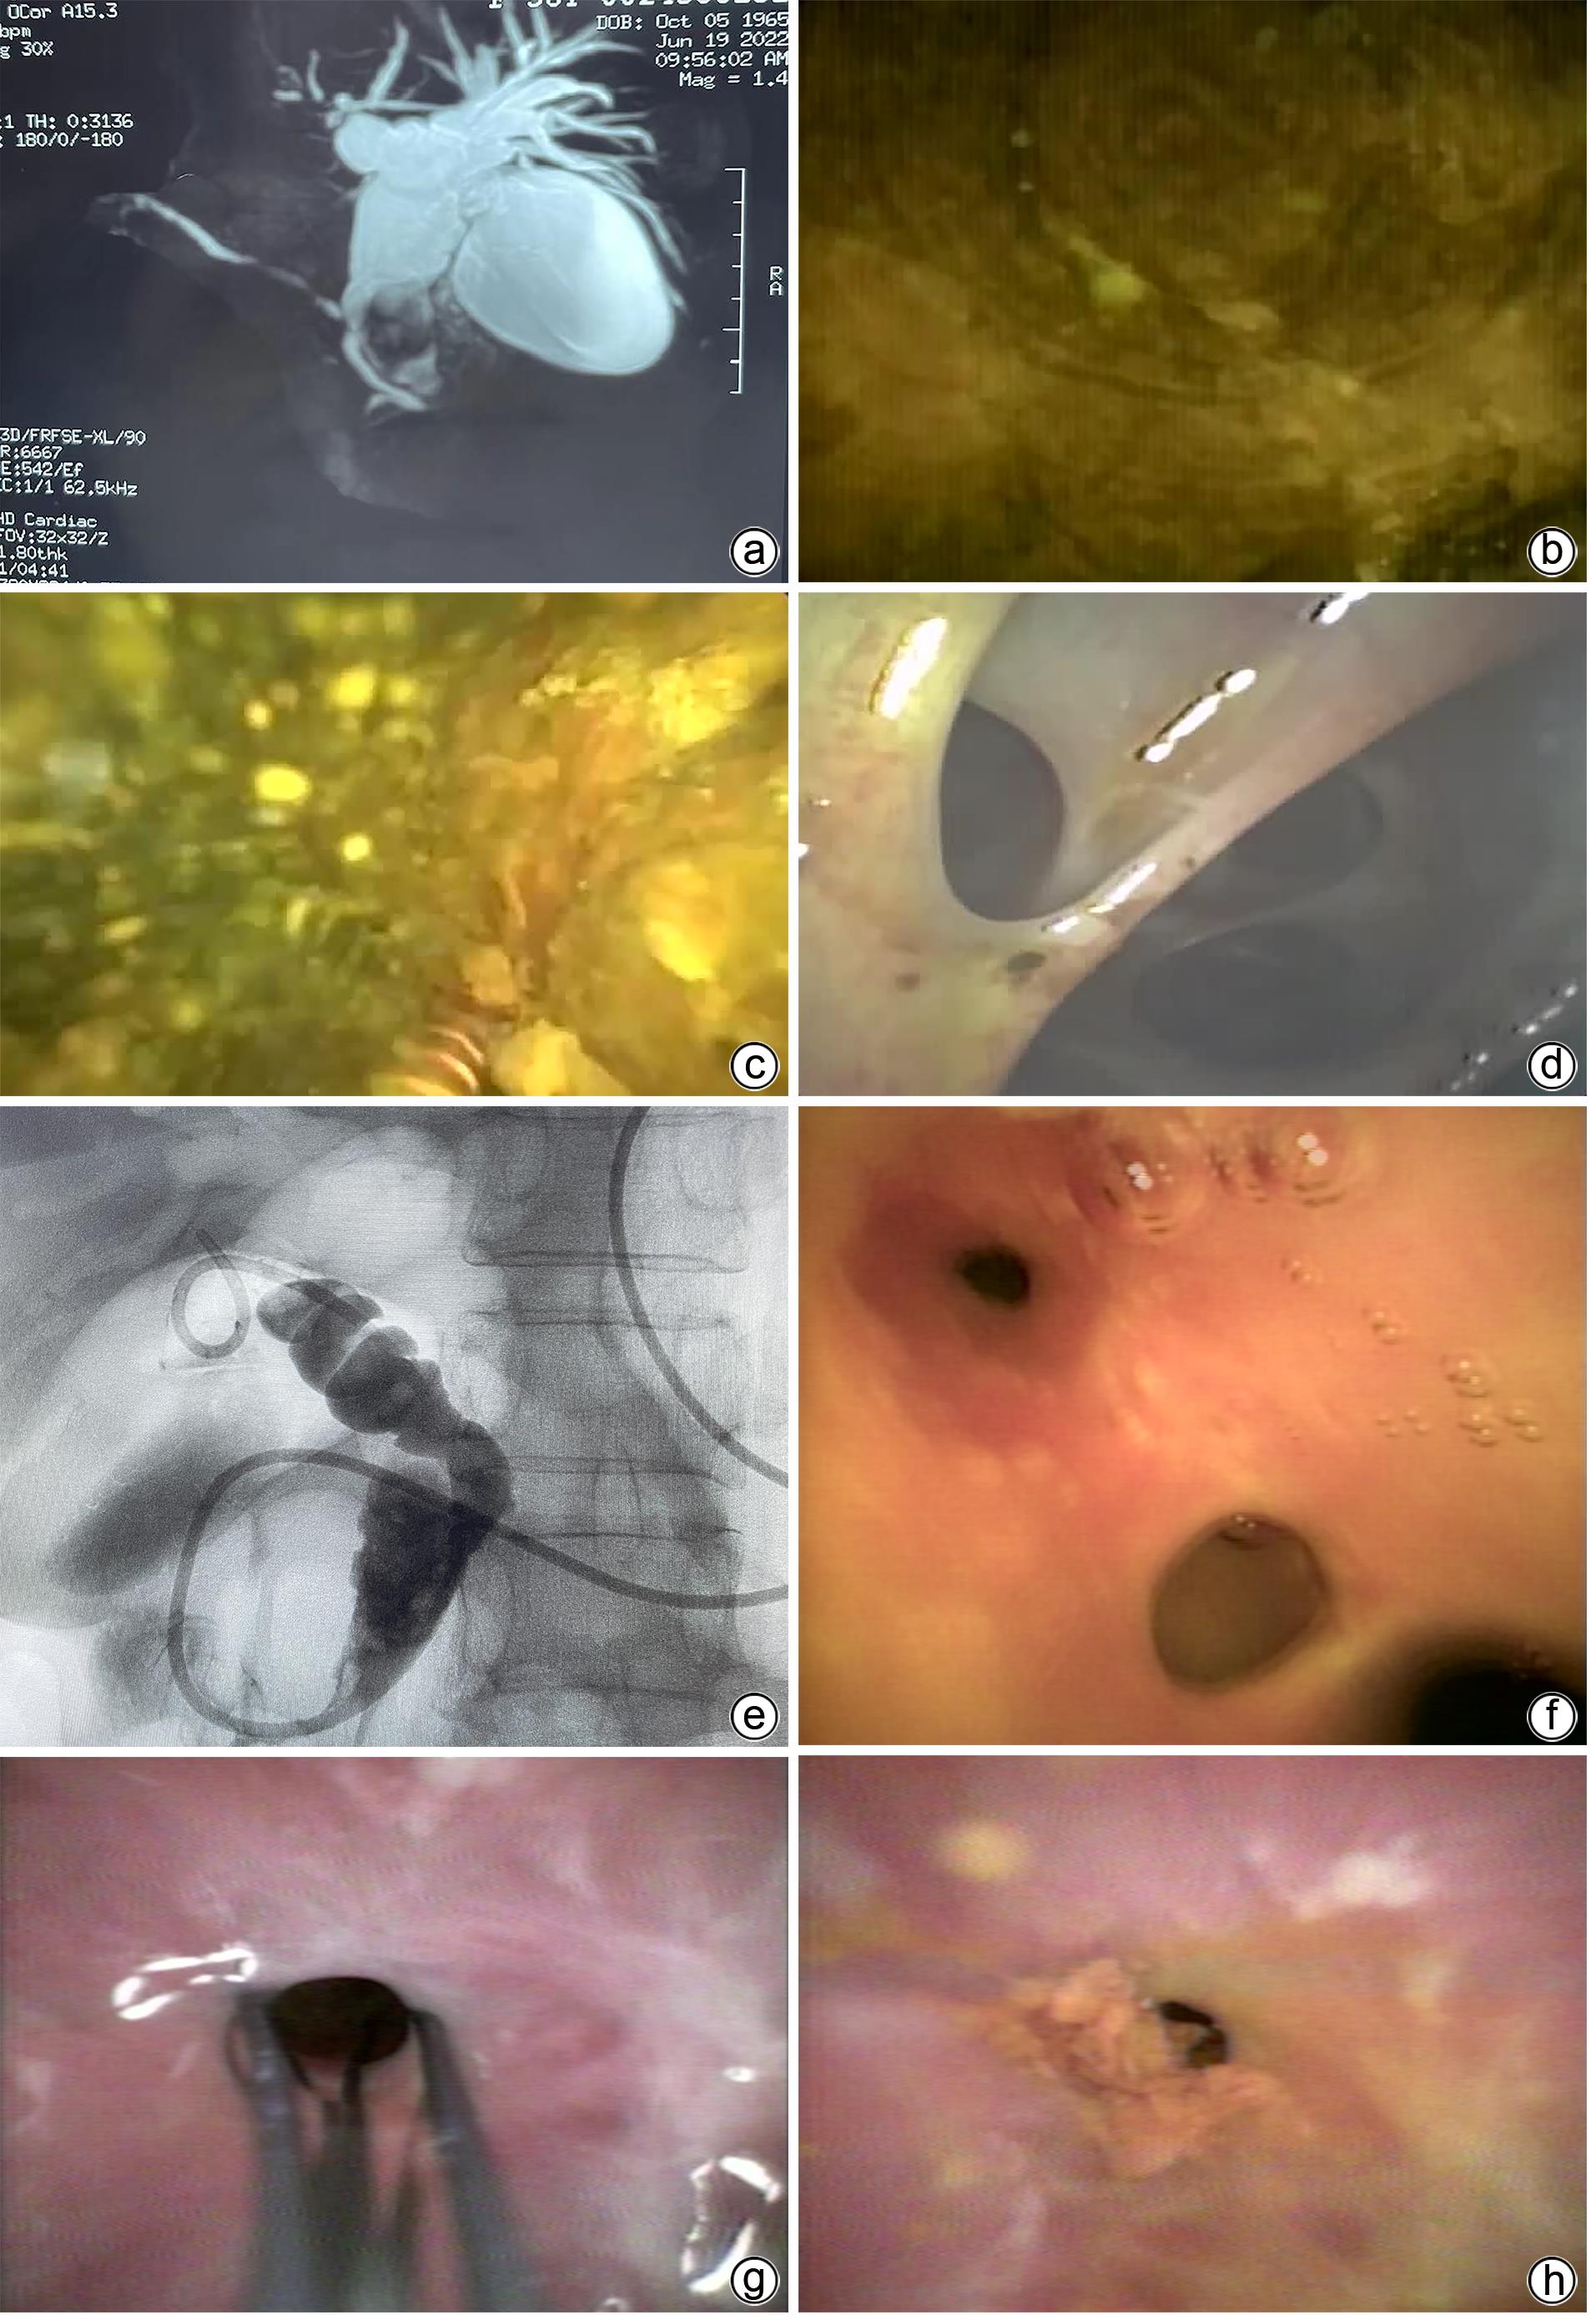

Preliminary identification of the cloning, expression, and function of Marmota himalayana type I interferon receptor β subunit

Ying TAO, Dongliang YANG, Baoju WANG, Yi LIU, Wenjia GUI, Zhi LI, Hebin FAN

2024, 40(2): 278-283. DOI: 10.12449/JCH240210

Abstract(796) HTML (304) PDF (920KB)(39)

Abstract:

Objective  To clone the gene of Marmota himalayana type ‍Ⅰ interferon receptor β subunit (mhIFNAR2), and to perform antibody preparation and functional identification.  Methods  RT-PCR was used for amplification in the spleen tissue of Marmota himalayana to obtain the sequence, which was cloned to the prokaryotic expression vector pRSET-B to express the recombinant protein. Electrophoresis and Western blot were used for identification. BALB/c mice were immunized with the recombinant protein to prepare the polyclonal antibody of its extracellular domain; immunohistochemistry, immunofluorescence assay, and Western Blot were used for identification, and the method of siRNA blockade was used to investigate its function. An analysis of variance was used for comparison of continuous data between multiple groups, and the least significant difference t-test was used for comparison between two groups.  Results  A fragment of mhIFNAR2 (149‍ ‍—‍ ‍1 ‍300 bp) was obtained from spleen tissue, which showed the highest homology of 98.05% in marmot. A prokaryotic expression plasmid was successfully constructed for expression of the extracellular domain of the mhIFNAR2(50-181aa) and was named pRSET-B.mhIFNAR2, and the recombinant protein expressed by this plasmid had a molecular weight of 27 kD, a purity of about 95% after purification, and a concentration of 160 μg/mL. After BALB/c mice were immunized with the purified recombinant protein, 1∶1 000 specific polyclonal antibodies were obtained, and immunohistochemistry and immunofluorescence assay showed the expression in cell membrane and cytoplasm. Among the three siRNAs synthesized, the siRNA starting from the 277 locus (siRNA277) could silence the expression of target genes and weaken the interferon signaling pathway compared with the blank control group and the negative control group (both P<0.05).  Conclusion  The fragment of mhIFNAR2 is obtained, and the polyclonal antibody for the extracellular domain of mhIFNAR2 is successfully prepared, with relatively high titer and specificity, and can be used for immunohistochemistry, immunofluorescence assay, and Western blot.